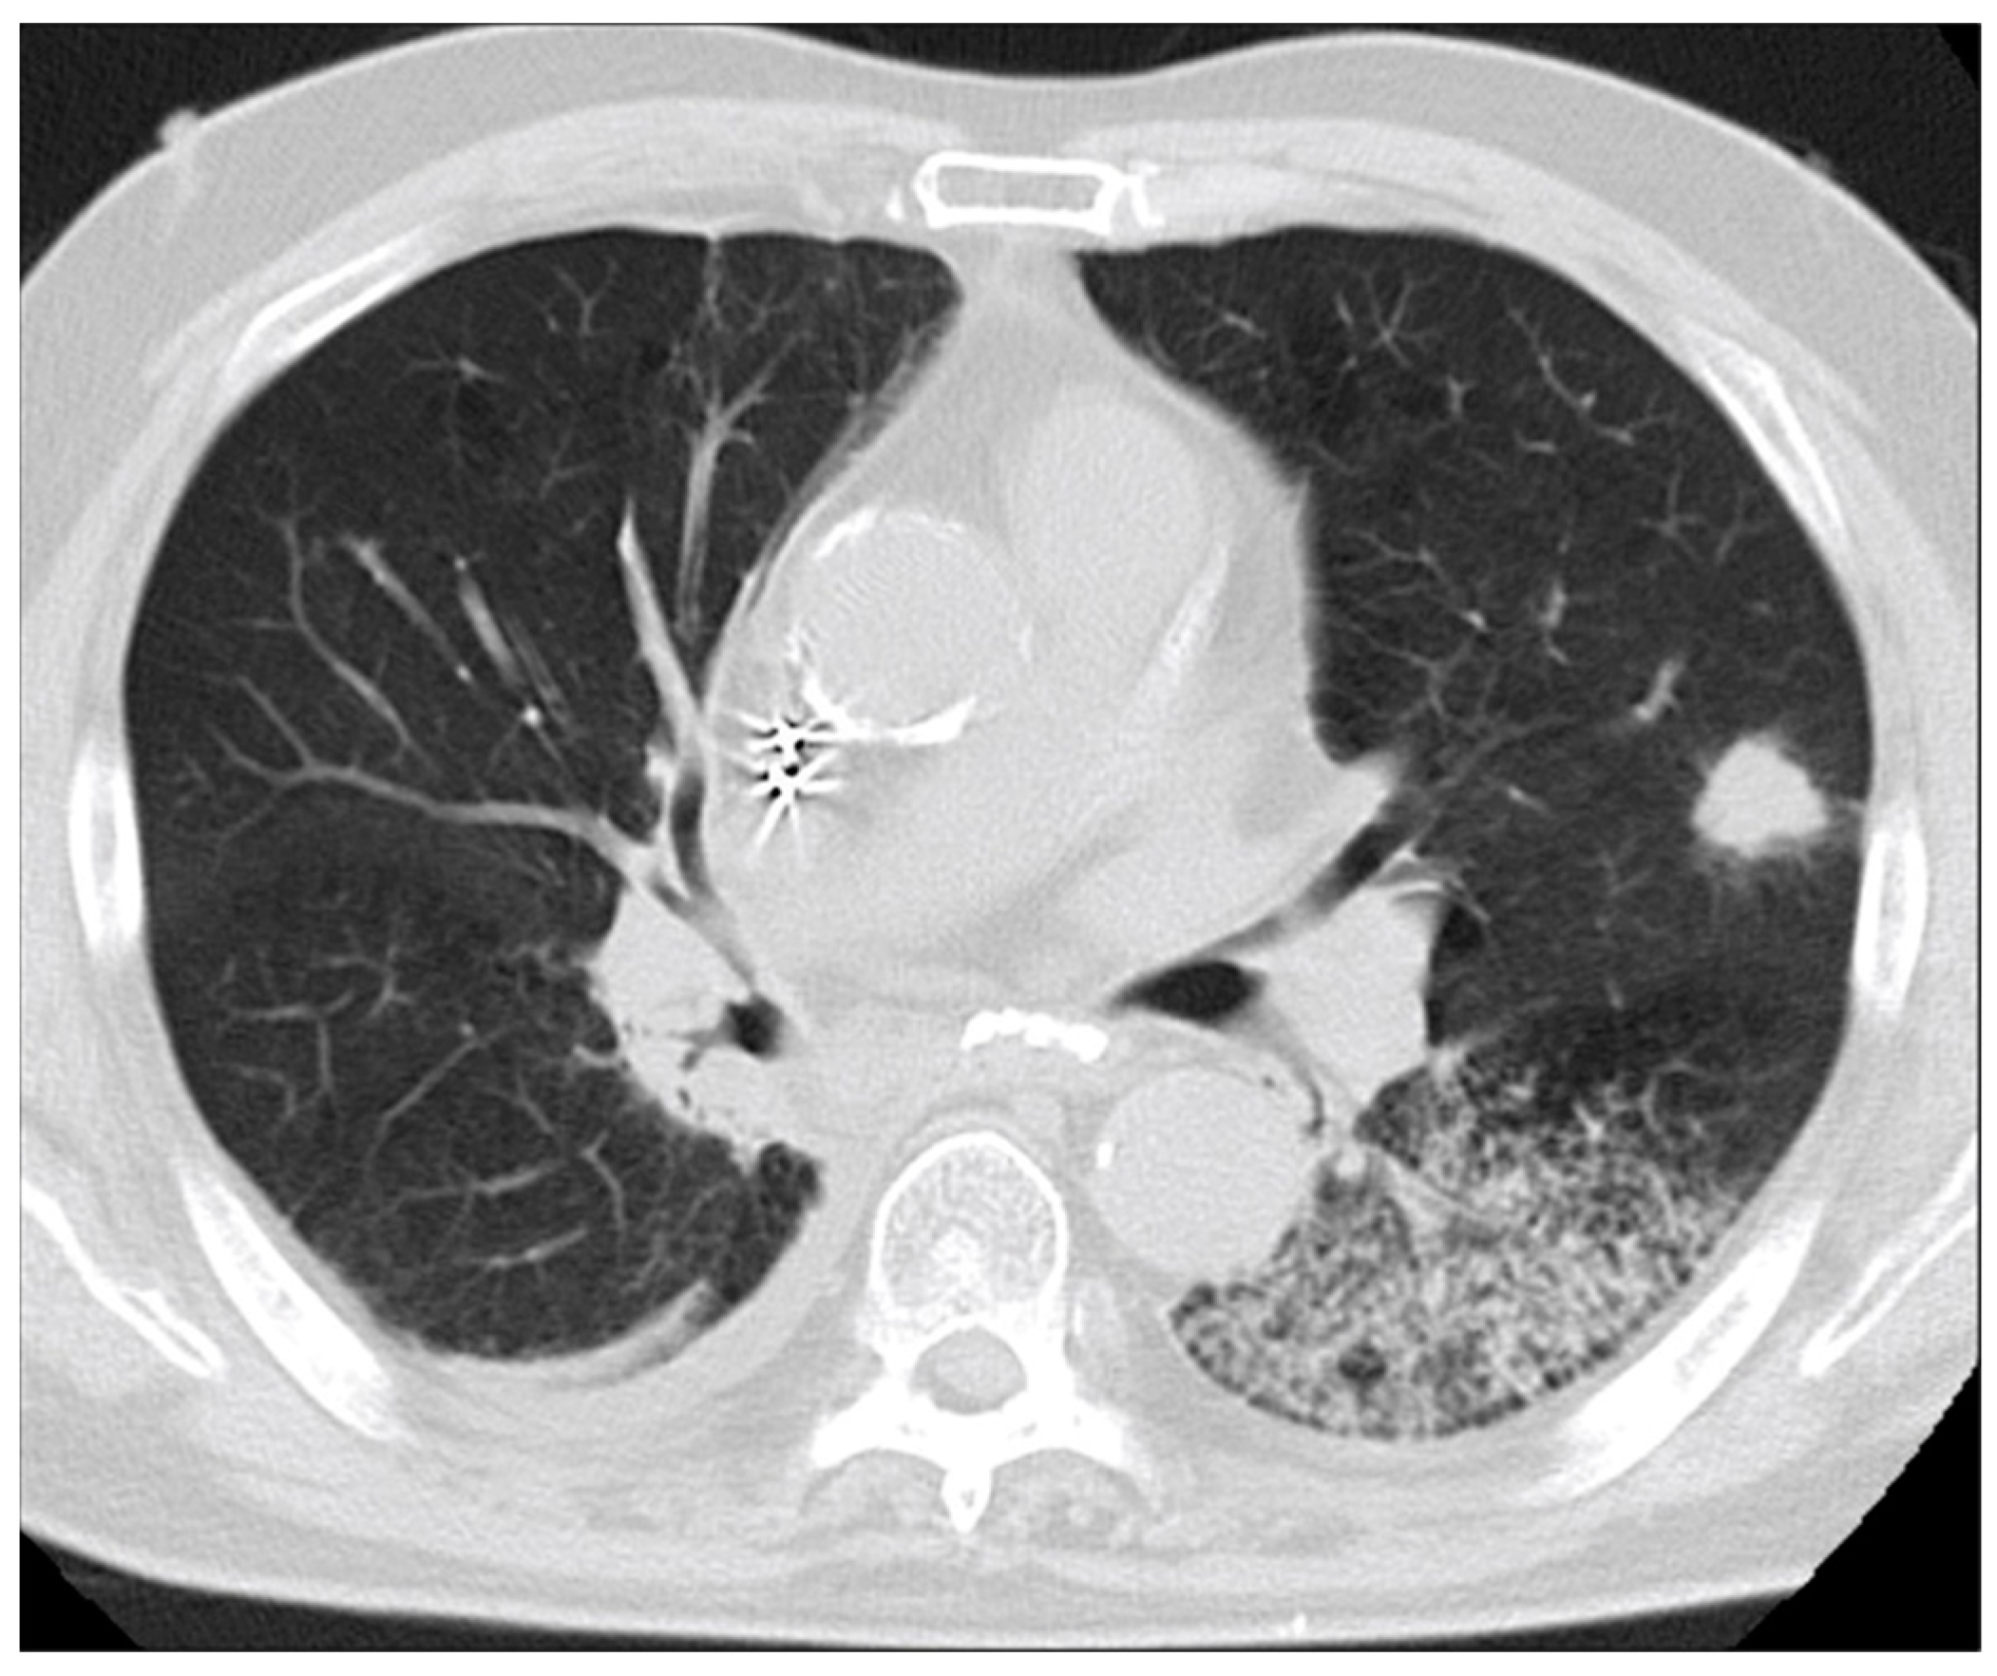

Programmed Death-Ligand 1-Positive Squamous Cell Carcinoma Spontaneously Regressed after Percutaneous Needle Biopsy

2. Case Report